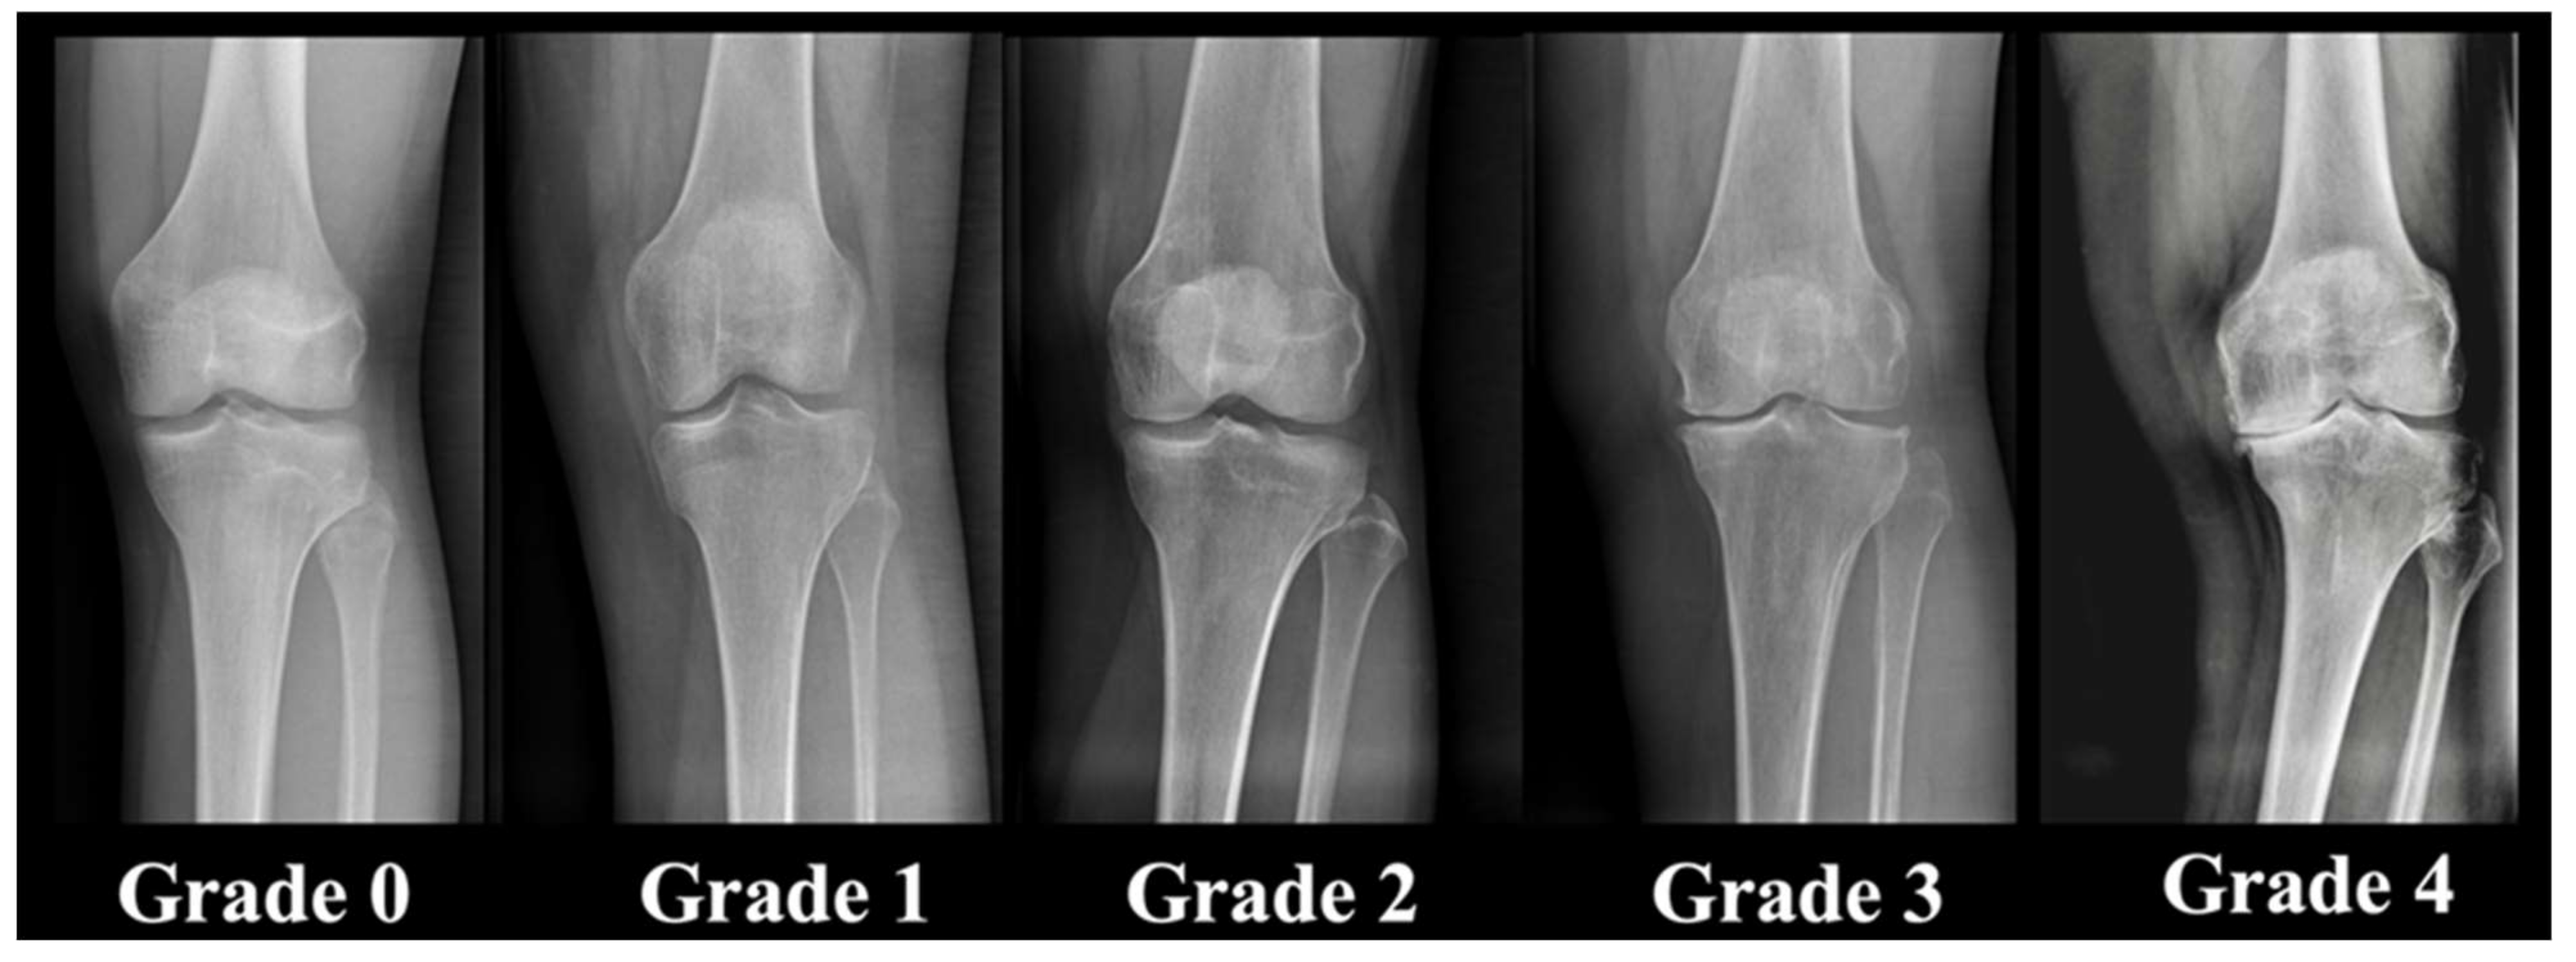

- Kellgren, J.H.; Lawrence, J.S. Radiological Assessment of Osteo-Arthrosis. Ann. Rheum. Dis. 1957, 16, 494–502. [Google Scholar] [CrossRef] [PubMed]

| Kellgren–Lawrence score | <0.0001 | ||

| 0 | - | 44.6% (n = 223) | |

| 1 | - | 55.4% (n = 277) | |

| 2 | 13.2% (n = 66) | - | |

| 3 | 23.4% (n = 117) | - | |

| 4 | 63.4% (n = 317) | - |